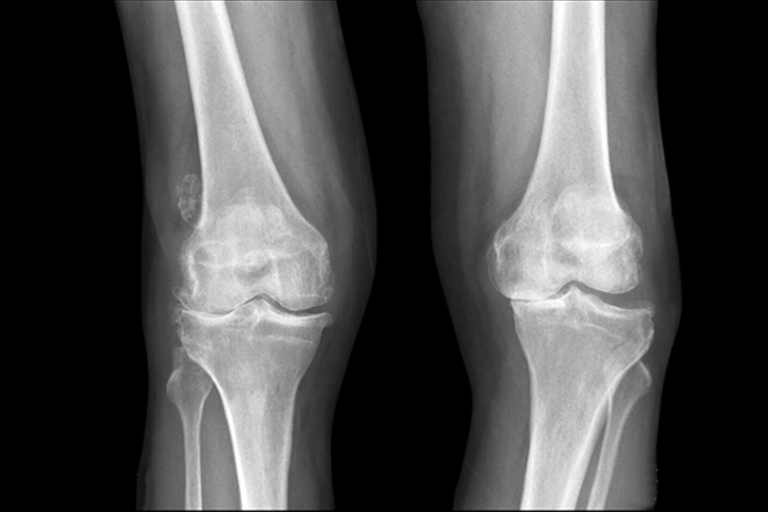

股関節・膝の痛み半月板損傷、前十字靭帯損傷、オスグッド病、ジャンパー膝、ランナー膝など

レントゲン、エコー(超音波)、必要に応じてMRI検査などを実施し、正確な診断を行います。